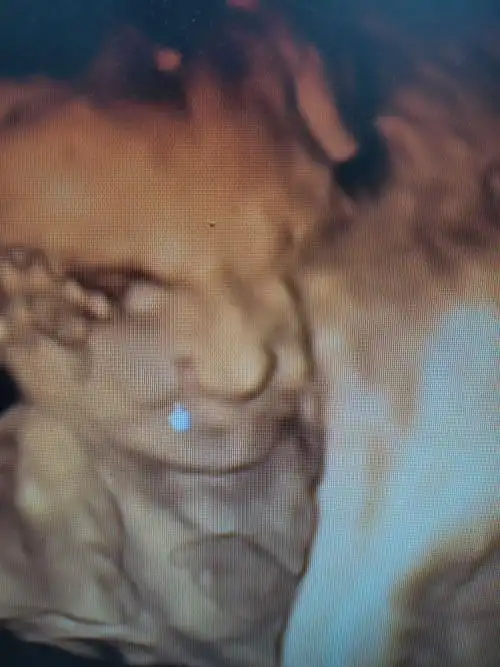

超声诊断胎儿唇腭裂